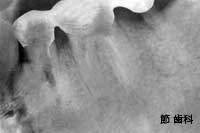

⑭ 平成7年に処置が施されたこの症例は、左下奥の2本を連続して喪失していたケースで、同部位にU字型の“ブレード型チタンコートPOI”タイプのインプラントを埋入し、隣在する歯と連結することで、欠損補綴を行ったものです。現在でも、メインテナンス等で来院されている患者さんで、15年以上が経過した、平成22年現在でも全く当時と同様に、現役で機能しています。